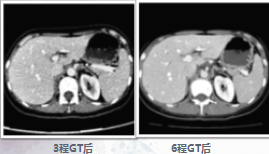

3程化疗后good PR

6程化疗后SD(较3程比较)

9程化疗后SD(较3程比较)